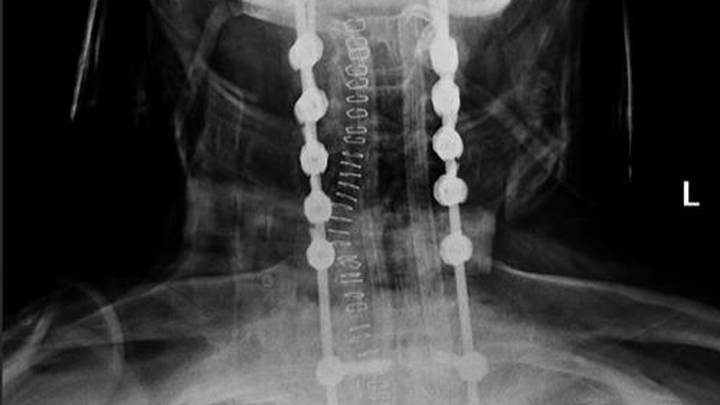

A few weeks ago, while visiting Hawaii, Buddy suffered a freak accident that left him with severe injuries — including breaks to all cervical vertebrae and 6 thoracic bones; basically, he broke his neck and upper back. Miraculously, there was no spinal cord injury amongst all of the damage.

My dad's surgery involved 24 titanium screws, two fused titanium rods, fusing C2-T6, and 53 staples to stabilize his cervical spine. He is now home, in recovery, facing a long and difficult road ahead.